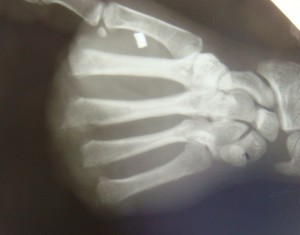

Случай 1. Пациент П-в., 27 лет. Был направлен на лечение в специализированный центр на 27 сутки после травмы кисти с диагнозом: Рана гранулирующая культи левой кисти. Травматический отрыв II-III-IV-V пальцев левой кисти на уровне метакарпальных костей (Рис. 5АБ).

Рис. 5. А – Цифровое фото раны гранулирующей культи левой кисти. Травматический отрыв II-III-IV-V пальцев левой кисти на уровне метакарпальных костей, концы которых предлежат в рануи покрыты тонким слоем грануляционной ткани. Б – Рентгенограмма левой кисти при поступлении в клинику.